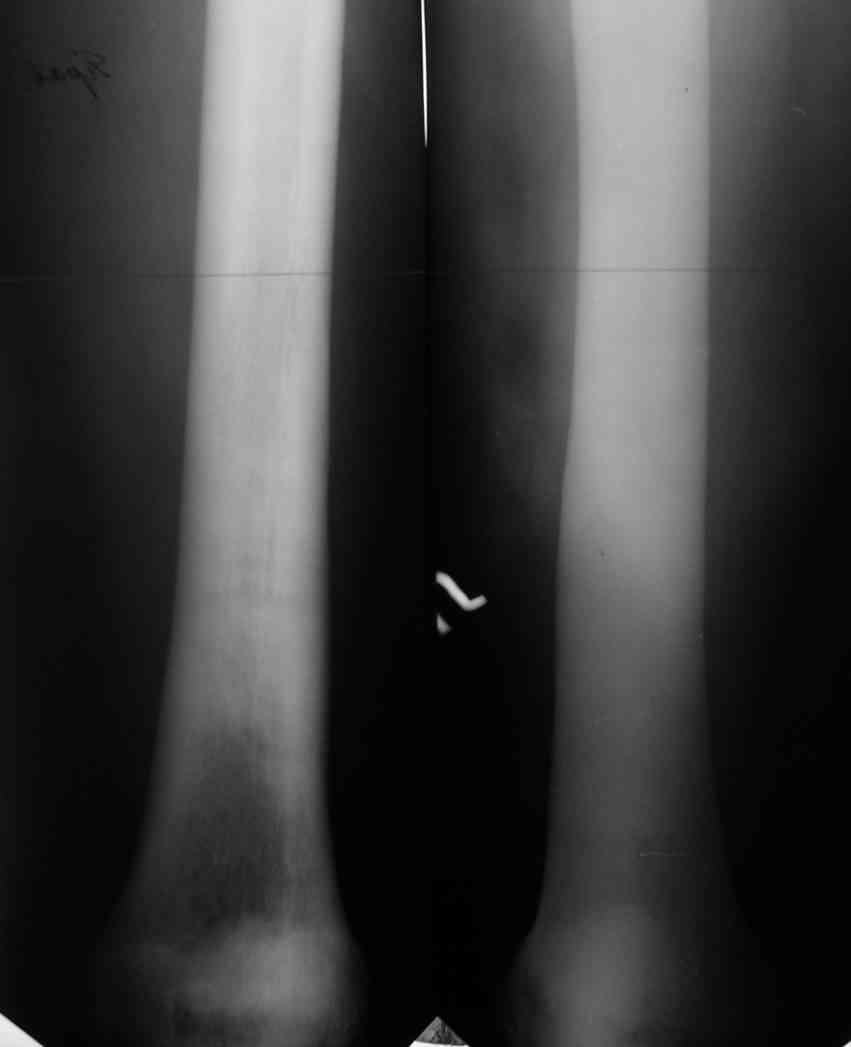

Уважаемый Константин Иванович! Полностью согласен с проф. Михайловым,

данный случай не похож на мраморную болезнь, при которой имеется

резкое, строго симметричное и генерализованное уплотнение костной

ткани (остеопетроз), и кость оказывается построенной преимущественно

из гомогенного компактного костного вещества. Для примера привожу

случай из архива нашего института (бедренные, плечевые кости и таз,

рис 1,2,3)